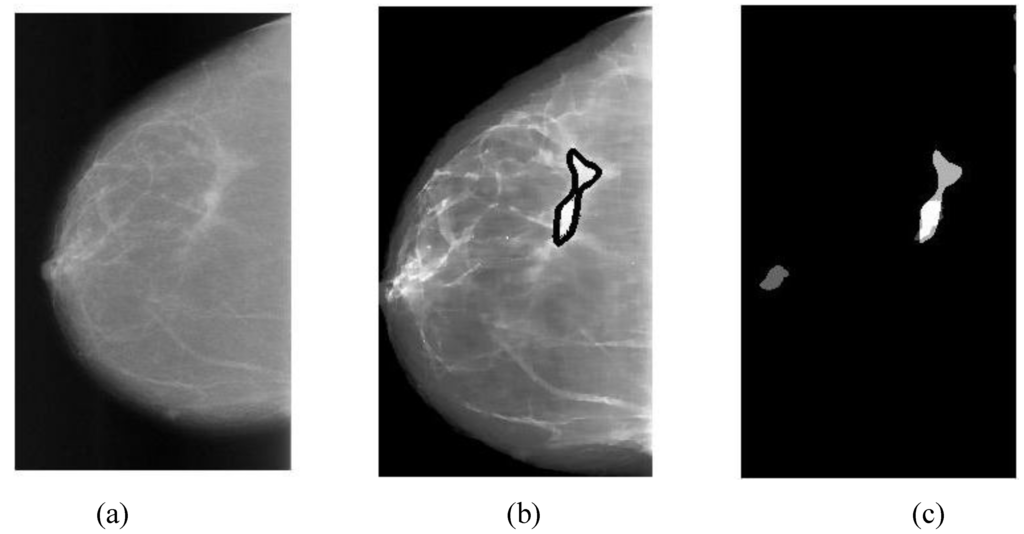

Four cancerous cases of malignant masses are shown in Figure 5, Figure 6, Figure 7 and Figure 8. The detailed descriptions and case analyses were given in figure captions. In each figure, Assessment and Subtlety of the first lesion are given. There are three panels in each figure: (a) is the original mammogram (ROI only); (b) is the preprocessed image (diffused and enhanced) with the annotations (detected by GCD, in heavy black outlines) and overlays (ground truths, in light black lines); (c) is the map of alarm segments generated from segmentation, overlapped on the overlays, and the probability values (PC) of alarm segments are also presented. In the DDSM database, the situation of a cancerous area is described by Assessment, rating from 1 to 5 (most advanced) and Subtlety, rating from 1 to 5 (most detailed). So a mass lesion of (Assessment, Subtlety) = (5, 5) is most easily detected. An early-stage mass detection was demonstrated in Figure 6, where (Assessment, Subtlety) = (1, 2).

Figure 10. GCD results of Case “3039_Left” (one malignant calcification with pleomorphic type and segmental distribution, assessment = 4, subtlety = 3): (a) Original mammogram; (b) Preprocessed image with one annotation ((PC = 0.71, detected by GCD, in heavy black outline) and one overlay (ground truth, in light black line)—an excellent match; (c) 9 alarm segments (PC = 0.71, 0.36, 0.35, 0.34, 0.34, 0.33, 0.33, 0.31, 0.31) overlapped on one overlay.

Two cancerous cases of malignant calcifications are shown in Figure 10 and Figure 11; whereas one healthy case is demonstrated in Figure 12 (where one false alarm is present after classification). The similar symbols and notions are used here. The case analyses are given in figure captions.